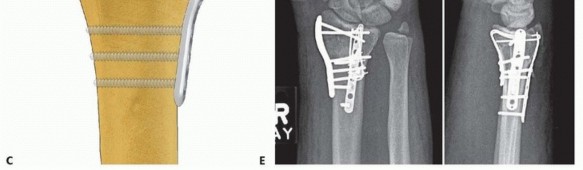

TECH FIG 8 • Radial column fixation with radial pin plate. A. Insertion of trans-styloid Kirschner wire. B,C. Creation of pin hook. D,E. Completion and impaction of pin hook. F,G. Completed radial column fixation. Select a distal pin hole and slide a radial pin plate over the trans-styloid Kirschner wire. Proximally, guide the plate under the tendons of the first dorsal compartment and secure it initially with a single 2.3-mm bone screw. Insert a second trans-styloid Kirschner wire through a nonadjacent distal pin hole. Use the previous technique to limit penetration of the Kirschner wire through the far cortex to 1 to 2 mm. Mark a reference point where the Kirschner wire crosses the surface of the plate. Withdraw the Kirschner wire 1 cm and cut it 1 cm or more above the reference mark ( TECH FIG 8B). Position the reference mark between the lower two posts of a wire bender and create a hook ( TECH FIG 8C). By starting the bend at the reference mark, this ensures that a Kirschner wire of proper length that extends 1 to 2 mm beyond the far cortex is created. Complete the bend with a pin clamp, overbending slightly to allow the hook to snap into an adjacent pin hole or over the edge of the plate ( TECH FIG 8D). With a free 0.045-inch Kirschner wire, predrill a hole to accept the end of the hook. Impact the Kirschner wire with a pin impactor and fully seat the hook ( TECH FIG 8E). Repeat the procedure with the second Kirschner wire. Complete proximal fixation with 2.3-mm cortical bone screws ( TECH FIG 8F,G). 2. ## Radial Column Fixation with Fixed-Angle Radial Column Plate 87 Expose and reduce the radial column with the technique described previously. Position the fixed-angle radial column plate and temporarily fix with a Kirschner wire both proximally and distally ( TECH FIG 9A). Confirm reduction of the radial column and plate position with the C-arm. Using fixed-angle drill guides, drill, measure, and insert locking fixation pegs of appropriate length into the distal fixed-angle holes in the plate and standard bone screws proximally into the shaft ( TECH FIG 9B-E).

TECH FIG 9 • Radial column fixation with fixed-angle radial column plate. A. Provisional placement of fixed-angle radial column plate. B. Drilling holes for distal fixed-angled pegs. C. Completed fixation. D. Unstable fracture injury films with segmental radial column comminution. E. Films 2 months postoperatively. Fixed-angle radial column support is used to avoid radial column shortening. 88 ## Ulnar Corner and Dorsal Wall Fixation Ulnar Pin Plate Through a dorsal approach, expose and reduce the dorsal ulnar corner fragment, dorsal wall fragment, or both. Insert a 0.045-inch Kirschner wire through the fragment ( TECH FIG 10A), angled proximally and slightly radially to purchase the far cortex of the proximal fragment. Insert structural bone graft into the metaphyseal defect if present to support the subarticular surface. If the plate is aligned along the pulnar border of the shaft, add a 15-degree torsional bend to the plate (twist the proximal end of the plate into slight supination). Often, a little extra extension can be contoured at the distal end of the plate ( TECH FIG 10B).